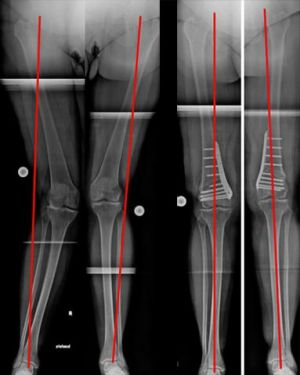

Individualisierte Vorgehensweise beim O-Bein (Bild 4). Infolge einer Verletzung der kniegelenksnahen, innenseitigen Wachstumsfuge resultierte dort eine diskrete Beinverkürzung mit O-Beinfehlstellung. Durch das aufklappende Verfahren wurden sowohl Beinlänge wie –achse ausgeglichen.